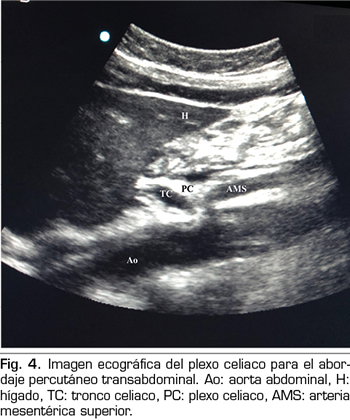

En los últimos años la ecografía ha ido ganando terreno a la fluoroscopia y al TAC en el manejo intervencionista del dolor. El primero en describir la técnica sobre el plexo celiaco fue Bhatnagar (31), pudiendo ser realizada percutáneamente en la cabecera del paciente y en decúbito supino, lo que da mayor comodidad tanto para el paciente como para el médico. Sin embargo, todavía no existen ensayos controlados y aleatorizados que comparen la neurólisis ecográfica abdominal del plexo celiaco frente al tratamiento sistémico opioide. La técnica se realiza utilizando una sonda convex (2-5 MHz), colocada inicialmente justo por debajo de la apófisis xifoides en el plano transversal, para identificar estructuras como hígado, estómago, intestino, venas portales, cava y aorta. Con la ayuda del Doppler, escaneamos caudalmente para identificar la bifurcación del tronco celiaco en las arterias hepática y esplénica, y más distalmente en la arteria mesentérica superior. Es entonces cuando giramos el transductor en el plano longitudinal, visualizando en la misma imagen la bifurcación de la aorta en el tronco celiaco y en la arteria mesentérica superior con el plexo celiaco rodeando estas estructuras. El  abordaje se realiza en plano, transabdominal, atravesando el hígado o el estómago, siempre y cuando no haya grandes vasos interfiriendo el recorrido de la aguja (Figura 4).

No se han reportado complicaciones con el abordaje percutáneo ecográfico; de todas formas, la literatura al respecto es insuficiente como para extraer conclusiones (32).